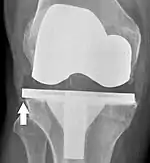

El aflojamiento de la prótesis puede estar indicado en la radiografía por espacios radiotransparentes delgados alrededor del implante, o más obviamente por el desplazamiento del implante.[48]

El reemplazo de rodilla se evalúa de forma rutinaria mediante rayos X, incluidas las siguientes medidas:

- CFF: ángulo del componente femoral frontal. Por lo general, se considera óptimo cuando se encuentra entre 2 y 7° en valgo.[55]

- CTF: ángulo del componente tibial frontal, que se considera óptimo cuando se encuentra en ángulo recto. En general, se ha encontrado que una posición en varo de más de 3 ° aumenta la tasa de falla de la prótesis.[55]

- La entalladura femoral anterior (el componente femoral que causa una reducción del grosor del fémur distal en la parte anterior) parece aumentar el riesgo de fracturas cuando excede aproximadamente 3 mm.[56]

- CTL: ángulo del componente tibial lateral (o sagital), que está idealmente posicionado de modo que la tibia esté flexionada de 0 a 7° en comparación con un ángulo recto con la placa tibial.[55]